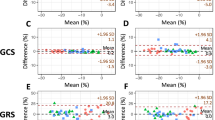

Intra-observer and inter-observer reproducibility of global strains

Intra- and inter-observer agreements of global myocardial strain for DRA and FT are shown in Table 4. DRA showed excellent intra- and inter-observer agreement in both iLVNC patients and normal controls. While for FT analysis, GRS of normal controls showed moderate intra-observer and poor inter-observer agreement. The intra- and inter-observer agreements of global strain derived from FT performed in iLVNC patients were higher than those in normal controls, especially the GRS.

Global radial strain (GRS) was statistically lower in EF ≥ 50% group compared with control group [GRS (DRA)/% vs. controls: 34.6 ± 7.0 vs. 37.6 ± 7.2, P < 0.001; GRS (FT)/% vs. controls: 37.4 ± 13.2 vs. 56.9 ± 16.4, P < 0.01]. ROC analysis of global strain values derived from DRA and FT demonstrated high area under curve (range, 0.743–0.854). DRA showed excellent intra- and inter-observer agreement of global strain in both iLVNC patients (ICC: 0.995–0.999) and normal controls (ICC: 0.934–0.996). While for FT analysis, global radial strain of normal controls showed moderate intra-observer (ICC: 0.509) and poor inter-observer agreement (ICC: 0.394).